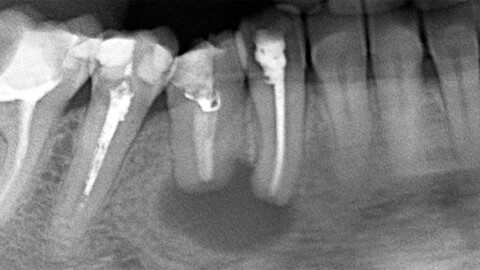

4. Рекомендации по визуализации:

• Лучший метод визуализации:

о Периапикальная рентгенография:

- Обладает наивысшим разрешением, позволяя обнаруживать ранние изменения; показывает легкое расширение пространства ПДС и ранние признаки разрушения твердой пластинки

- Традиционно используется для проведения измерений при вмешательстве на корнях:

КЛКТ лишь недавно была адаптирована для эндодонтического анализа

- КТ и КЛКТ позволяют обнаружить периапикальный рарефицирующий остеит:

Визуализация может быть затруднена из-за артефактов от металла, особенно рядом с имплантами